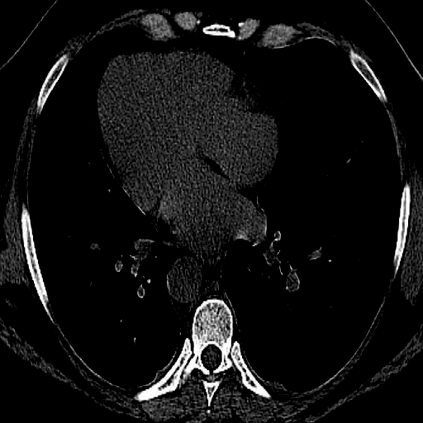

The novel coronavirus disease 2019 (COVID-19) has been spreading rapidly around the world and caused significant impact on the public health and economy. However, there is still lack of studies on effectively quantifying the lung infection caused by COVID-19. As a basic but challenging task of the diagnostic framework, segmentation plays a crucial role in accurate quantification of COVID-19 infection measured by computed tomography (CT) images. To this end, we proposed a novel deep learning algorithm for automated segmentation of multiple COVID-19 infection regions. Specifically, we use the Aggregated Residual Transformations to learn a robust and expressive feature representation and apply the soft attention mechanism to improve the capability of the model to distinguish a variety of symptoms of the COVID-19. With a public CT image dataset, we validate the efficacy of the proposed algorithm in comparison with other competing methods. Experimental results demonstrate the outstanding performance of our algorithm for automated segmentation of COVID-19 Chest CT images. Our study provides a promising deep leaning-based segmentation tool to lay a foundation to quantitative diagnosis of COVID-19 lung infection in CT images.